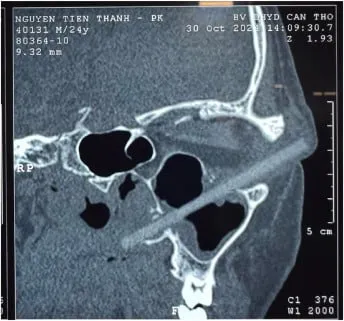

24-летнему мужчине лечение не помогло, глаз стал более опухшим. Тогда, как пишет Оdditycentral, ему вновь проверили зрение, которое оказалось 10 из 10. И только после КТ выяснилось, у человека в глазнице застряло инородное тело длиной 9 см. Это оказалась обычная деревянная палочка для еды. Она прошла не повредив сам глаз и уперлась в боковую носовую стенку.